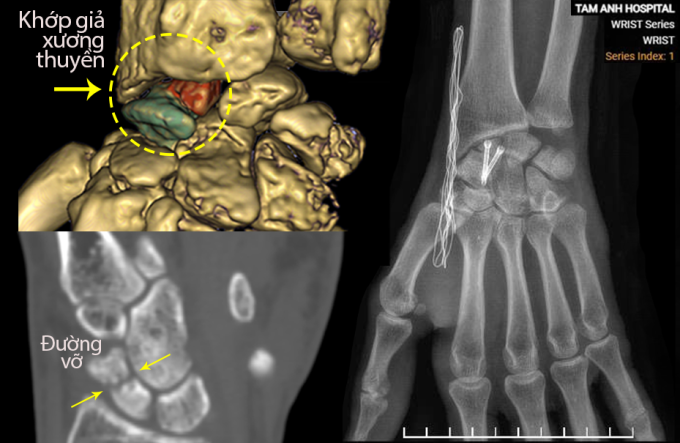

Anh Tuấn về Bệnh viện Đa khoa Tâm Anh Hà Nội chụp X-quang và cắt lớp vi tính CT, phát hiện khớp giả ở xương thuyền. TS.BS Chế Đình Nghĩa, Phó khoa Chấn thương Chỉnh hình, giải thích xương từng bị gãy nhưng điều trị không hiệu quả nên không liền, lâu ngày tạo ra một khoảng hở giống như khớp gây đau đớn, hạn chế vận động và thường xuyên tái phát.

Bác sĩ Nghĩa đánh giá tình trạng khớp giả của anh Tuấn nghiêm trọng vì kéo dài nhiều năm, tái phát nhiều lần. Bệnh nhân còn lao động nặng hàng ngày khiến các đầu xương cọ xát liên tục, không liền được mà còn khiến cơ thể phản ứng lại, tích tụ canxi tại vị trí tổn thương làm đặc hai đầu xương, chai cứng như đá. Khớp giả tồn tại ngày càng đau nặng hơn, gây thoái hóa sớm khớp cổ tay có thể khiến bệnh nhân mất khả năng vận động.

Anh Tuấn được phẫu thuật cố định ổ khớp giả xương thuyền sử dụng xương ghép tự thân. Bác sĩ rạch đường mổ 3 cm trên vùng cổ tay, dùng khoan mài sạch hai diện gãy của ổ khớp giả, loại bỏ các đầu "xương hóa đá". Sau đó, êkíp mở đường mổ ở hông bệnh nhân lấy một mảnh xương xốp giữa mào chậu ghép lên khoảng hở giữa hai đầu gãy xương thuyền vừa xử lý. Các đoạn xương được cố định bằng hai vít chuyên dụng.

Quá trình phẫu thuật được thực hiện dưới máy chụp X-quang liên tục (C-arm), giúp xác định chính xác vị trí khớp giả, trục đặt vít Herbert theo kế hoạch mổ 3D, tránh lệch chỉ vài độ có thể khiến vít xuyên khỏi xương thuyền vốn rất nhỏ.